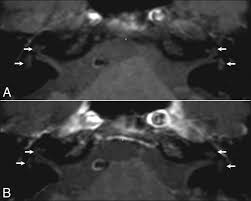

В режиме Т1 определяется нормальный или сниженный сигнал от структур улитки и слухового нерва, возможна асимметрия калибра преддверно-улиткового нерва в канале внутреннего слухового прохода.

В режиме Т2 визуализируется снижение сигнала от эндолимфы или ликвора внутреннего слухового прохода при отёке, гипоплазии или атрофии преддверно-улиткового нерва.

В режиме с подавлением сигнала от жира подчёркиваются тонкие контуры слухового нерва и его окружения, выявляется разница в толщине и структуре между сторонами.

В режиме с контрастированием определяется накопление контрастного вещества при наличии воспаления, неоплазии или сосудистой мальформации.

- Толщина и структура преддверно-улиткового нерва в зоне канала и мостомозжечкового угла фиксируются по сигнальным характеристикам.

- Протяжённость и форма внутреннего слухового прохода оцениваются при подозрении на его сужение или расширение, что важно для исключения врождённых аномалий.

- Состояние улитки и лабиринта, включая эндолимфатический мешок, анализируется при подозрении на гидропс или врождённую дисплазию.